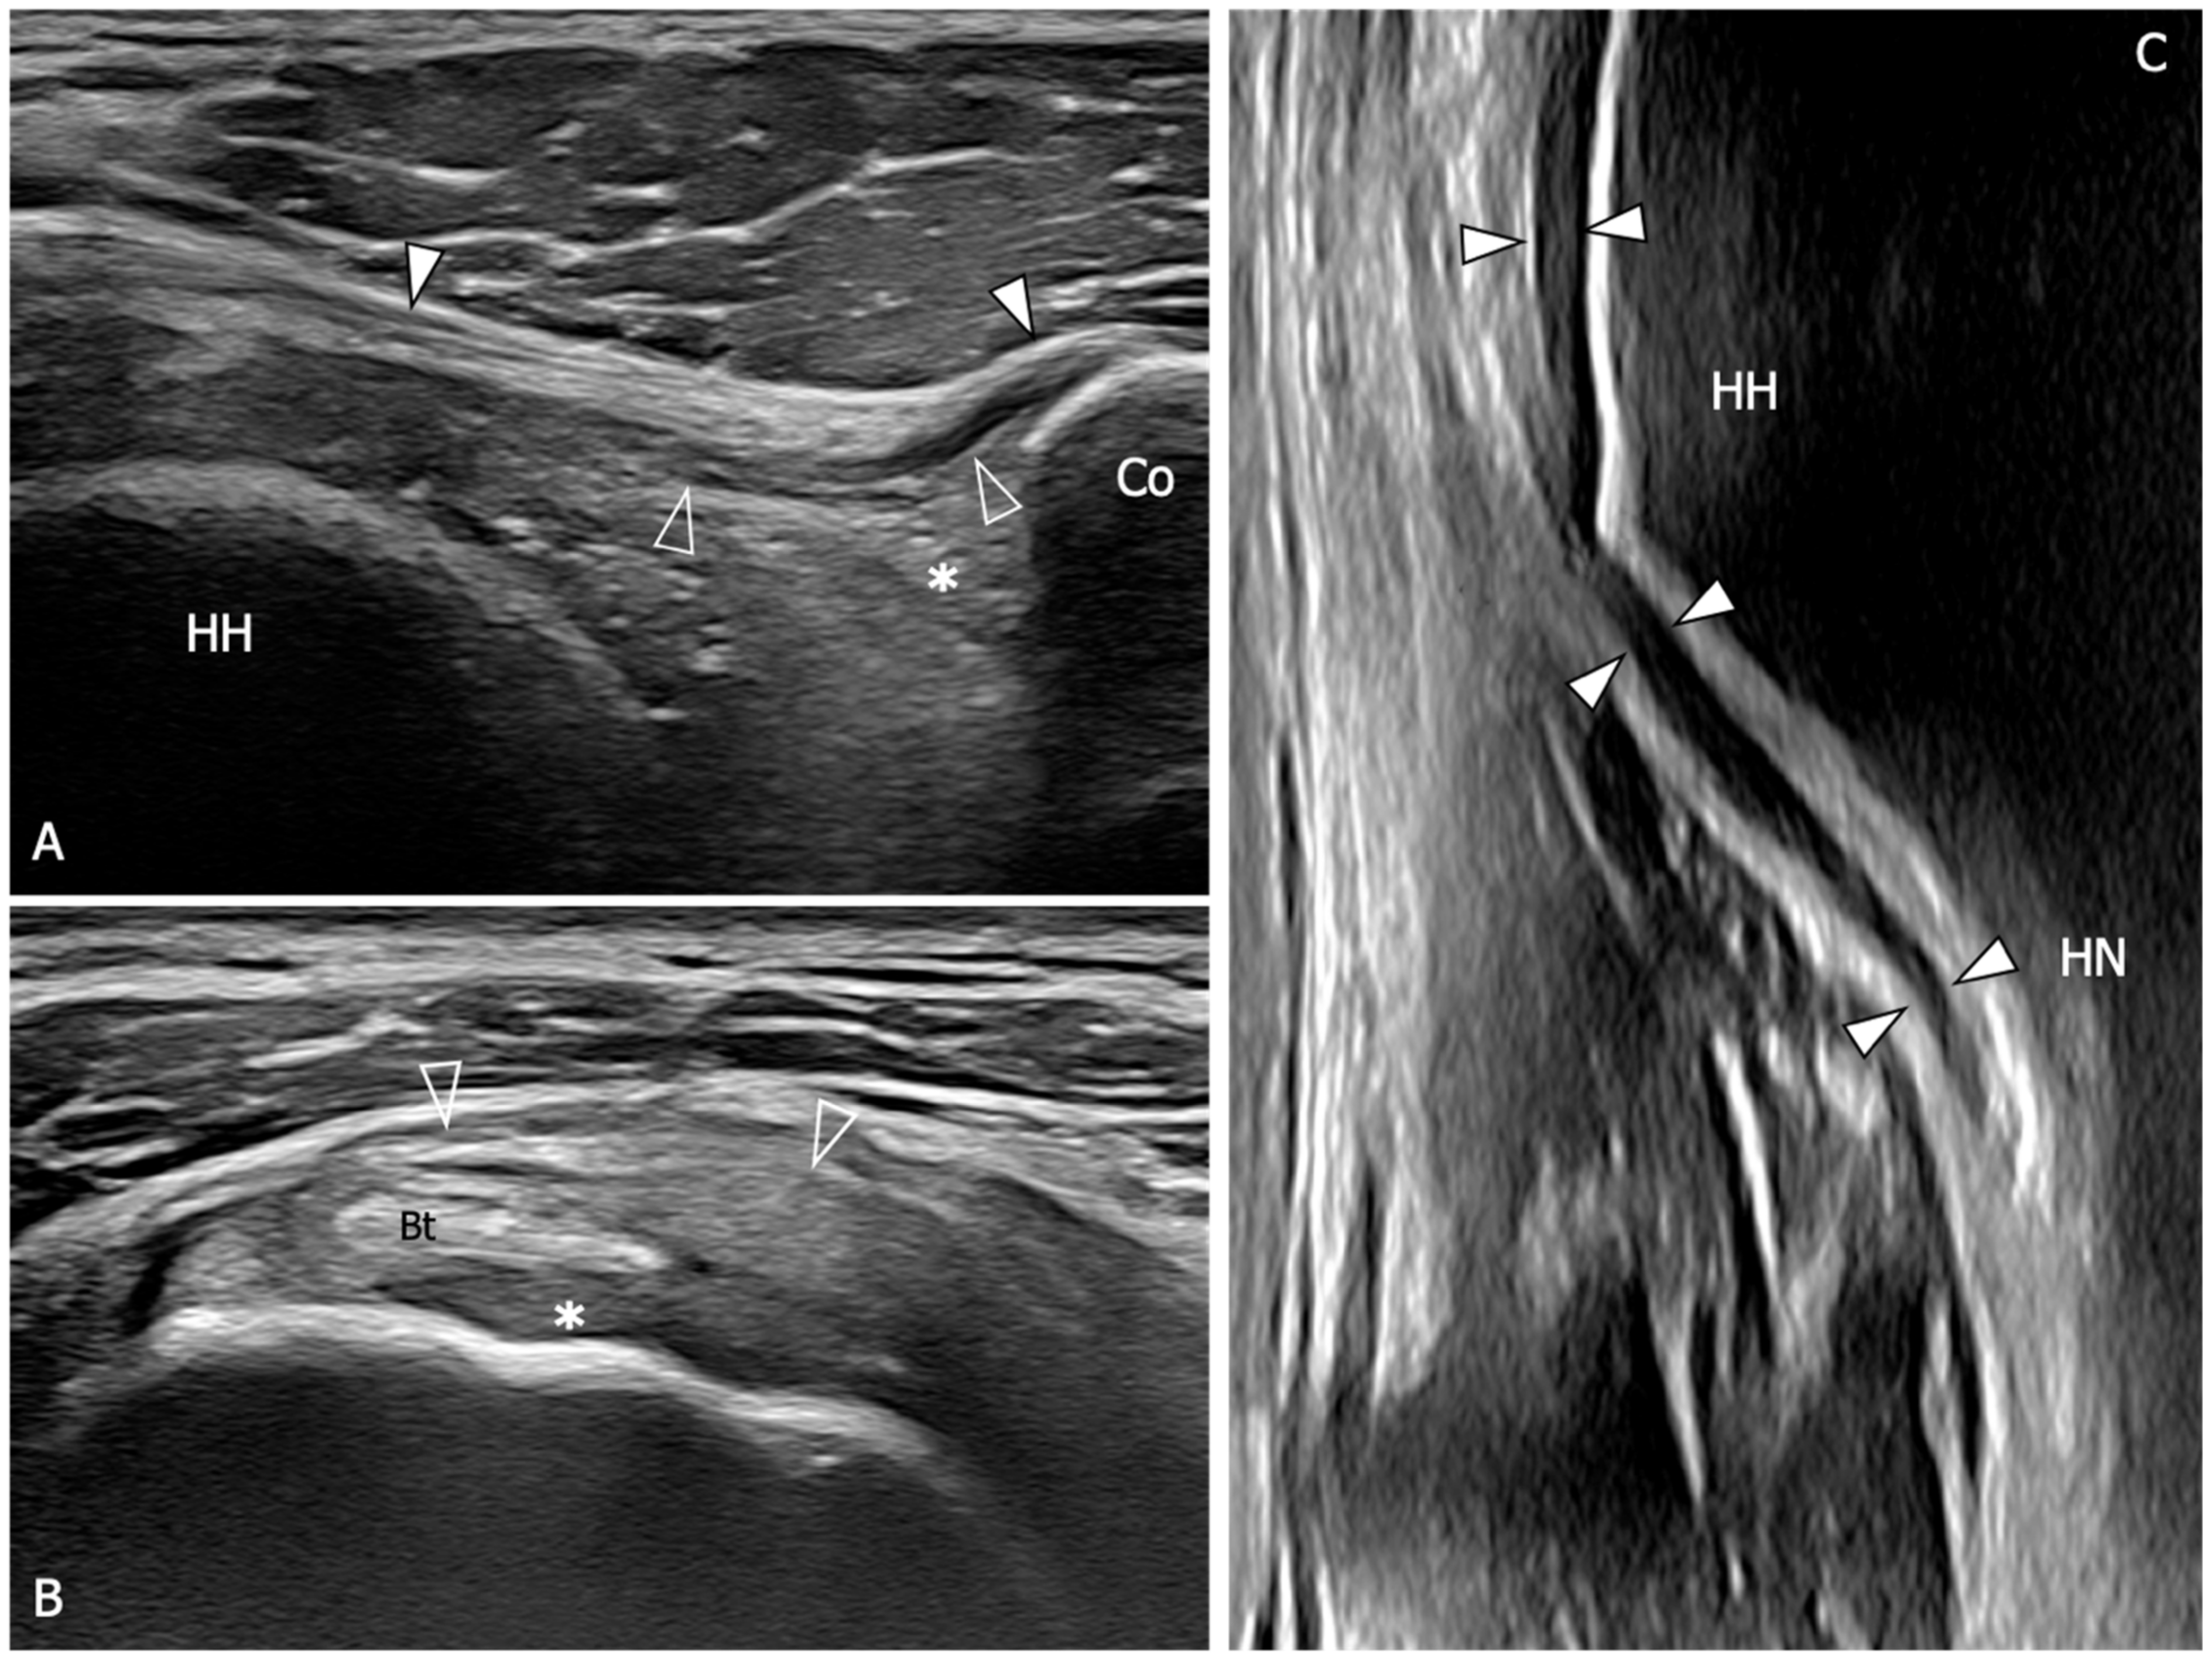

Figure 5.

Glenohumeral joint capsule and pericapsular ligaments, normal US findings. (A) Oblique transverse 18–5 MHz US image shows the normal thin and fibrillar appearance of the coracohumeral ligament (outlined arrowheads), which is demonstrated connecting the coracoid (Co) and humeral head (HH) in a deeper position respective to the coracoacromial ligament (arrowheads). Note the homogeneous and hyperechoic appearance of the subcoracoid fat (asterisk). (B) Short-axis 18–5 MHz US image shows the distal part of the coracohumeral ligament (outlined arrowheads) in the area of the rotator interval and the biceps pulley (asterisk). Bt, long head of the biceps tendon. (C) Longitudinal 18–5 MHz US obtained orienting the probe parallel to the humerus in the axillary region shows the inferior capsule (arrowheads) overlying the humeral head (HH) and folding over the humeral neck (HN).

Figure 6.

US findings in a 53 year old woman with adhesive capsulitis. (A) Oblique transverse 18–5 MHz US image demonstrates the markedly thickened coracohumeral ligament (outlined arrowheads), which has lost the normal fibrillar echotexture and appears homogeneously hypoechoic due to fibrotic changes and degeneration of the fibers. Note the presence of hypoechoic synovial tissue in the subcoracoid triangle (asterisk). Arrowheads, coracoacromial ligament. (B) Short-axis 18–5 Mhz US evidences the thickening and fibrotization of the coracohumeral ligament (arrowheads) and the biceps pulley (asterisks) in the rotator interval. (C) Longitudinal 18–5 MHz US image shows a significant thickening of the inferior capsule (arrowheads). HH, humeral head; Co, coracoid; Bt, long head of the biceps tendon; HN, humeral neck.

Regarding the coracohumeral ligament mean thickness in healthy subjects and patients with AC, a lack of consensus can be found in different US studies, intuitively depending on the scanning technique adopted for the identification and measurement of this structure. Homsi et al. evaluated the coracohumeral ligament with US by measuring its thickness in both long- and short-axis cross-sections and considering the maximal thickness value obtained. Using this method, an average coracohumeral ligament thickness of 3 mm was demonstrated in shoulders affected by AC. In comparison, painful shoulders exhibited an average coracohumeral ligament thickness of 1.39 mm, whereas asymptomatic shoulders had an average coracohumeral ligament thickness of 1.34 mm [64]. In a study by Tandon et al., the thickness of the coracohumeral ligament was measured in the oblique axial plane while keeping the arm externally rotated. Even with this method, patients with AC exhibited a significantly higher coracohumeral ligament thickness (1.2 mm) compared to both the group with painful shoulders (0.54 mm) and the control group (0.4 mm) [65]. In patients with AC, Lee et al. found a higher prevalence of distension of the long head of biceps tendon sheath in the affected shoulder respect to the contralateral side while Park et al. demonstrated a greater amount of effusion within the long head biceps tendon sheath in patients with AC compared to patients with other causes of painful shoulder [66,67]. Moreover, they demonstrated a negative correlation between the amount of effusion within the long head of the biceps tendon sheath and the glenohumeral range of motion. However, it has to be considered that any condition determining inflammation of the joint capsule may lead to fluid distension of the long head of the biceps tendon sheath and consequently this finding cannot be considered specific for AC.